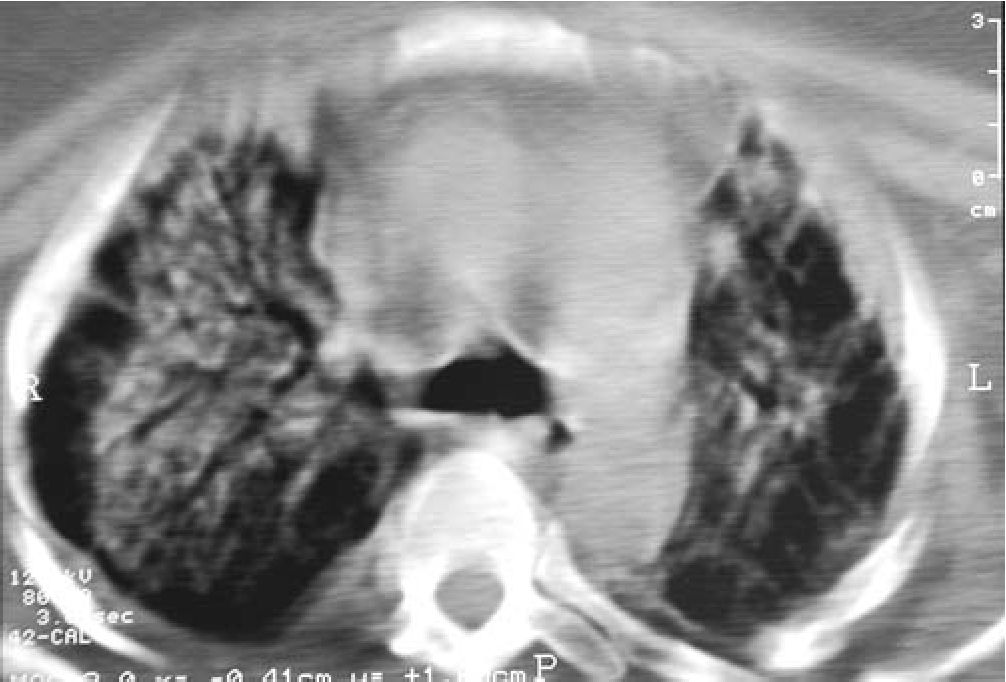

На всех этапах ИВЛ и последующего ступенчатого режима отлучения и реабилитации больная находилась в сознании, что позволило в более ранние сроки прейти от зондового на обычный путь приема адекватного лечебного питания. Период отлучения и реабилитации оказался более сложным, продолжительным, с длительно сохраняющимися участками консолидации легочной ткани (рис. 5).

Рис. 5. Масивная консолидация ткани легких

По мере купирования инфильтрации в легких на этапе отлучения от респиратора достаточно долго сохранялась физическая и психологическая зависимость от кислорода и респиратора. Результаты последующего контрольного обследования подтвердили клинический диагноз формирующегося пневмофиброза, что потребовало специальной реабилитационной терапии. Общая продолжительность респираторной поддержки составила 56 дней. Имея определенный опыт использования гелий-кислородных смесей при некоторых заболеваниях легких, мы в процессе длительной ИВЛ у данной больной, к сожалению, по ряду причин применить его не смогли.

Далее в течение 18 дней больная проходила курс реабилитации в пульмонологическом центре Краевой клинической больницы № 1. На момент написания данной статьи от начала заболевания прошло более 4 мес. с клинически положительными результатами на фоне продолжающейся реабилитации. В течение первых 2 нед. после выписки сохранялась психологическая и физическая зависимость от кислорода. В дальнейшем кислородная зависимость была преодолена, при сохранении умеренной одышки пациентка стала «мобильна» в пределах дома и поездок по городу. На КТ грудной клетки выявлено формирование интерстициального фиброза в зонах предшествующего поражения ткани легких (рис. 5).